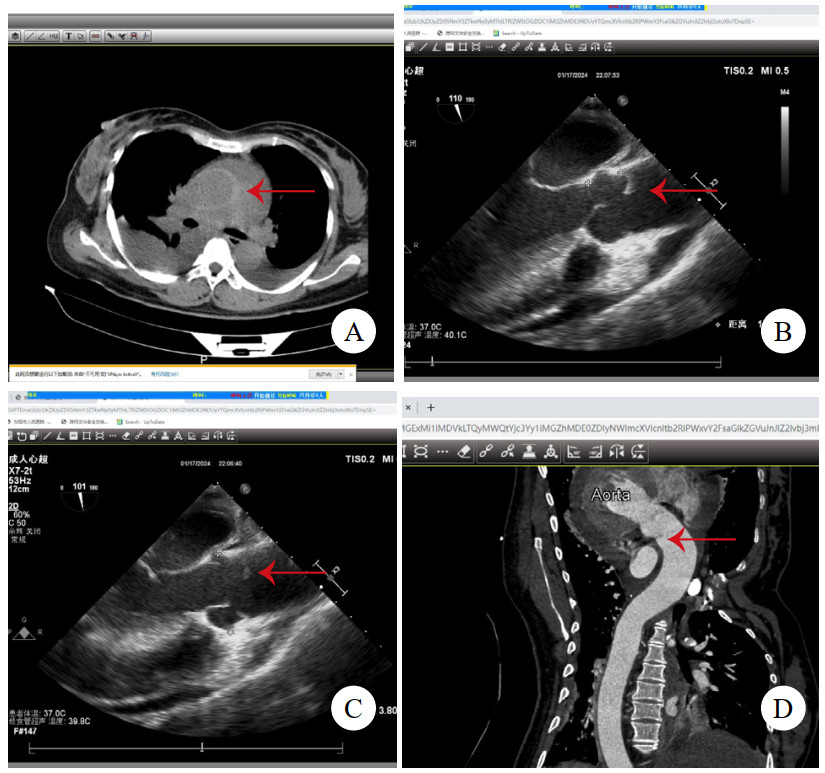

病例2,男,47岁,因“突发背痛伴胸闷1 h”入院。查心电图提示下壁导联ST段抬高0.1 mv,TTE提示节段性室壁运动异常,升主动脉及窦内径增宽,肌钙蛋白阴性,考虑“急性心肌梗死”。行急诊冠脉造影术,见冠状动脉通畅,加行主动脉造影见根部后壁斜行龛影(图 2A)。予查主动脉CTA,见主动脉根部左冠状动脉开口上方条状影(图 2B),该处主动脉直径为44 mm,升主动脉周围少量心包积血(图 2C),提示LIT。建议急诊开胸手术,患方自行至外院行升主动脉置换术,术中所见符合LIT,术后2个月至本院复查TTE,见升主动脉人工血管通畅(图 2D),无室壁运动异常。后门诊随访5年,情况平稳。

注:A为主动脉造影,箭头示根部后壁斜行龛影;B为主动脉CTA,箭头示左冠状动脉开口上方条状影;C为箭头示升主动脉周围少量心包积血;D为TTE见升主动脉人工血管通畅 图 2 例2患者主动脉根部造影、术前CT及术后TTE影像